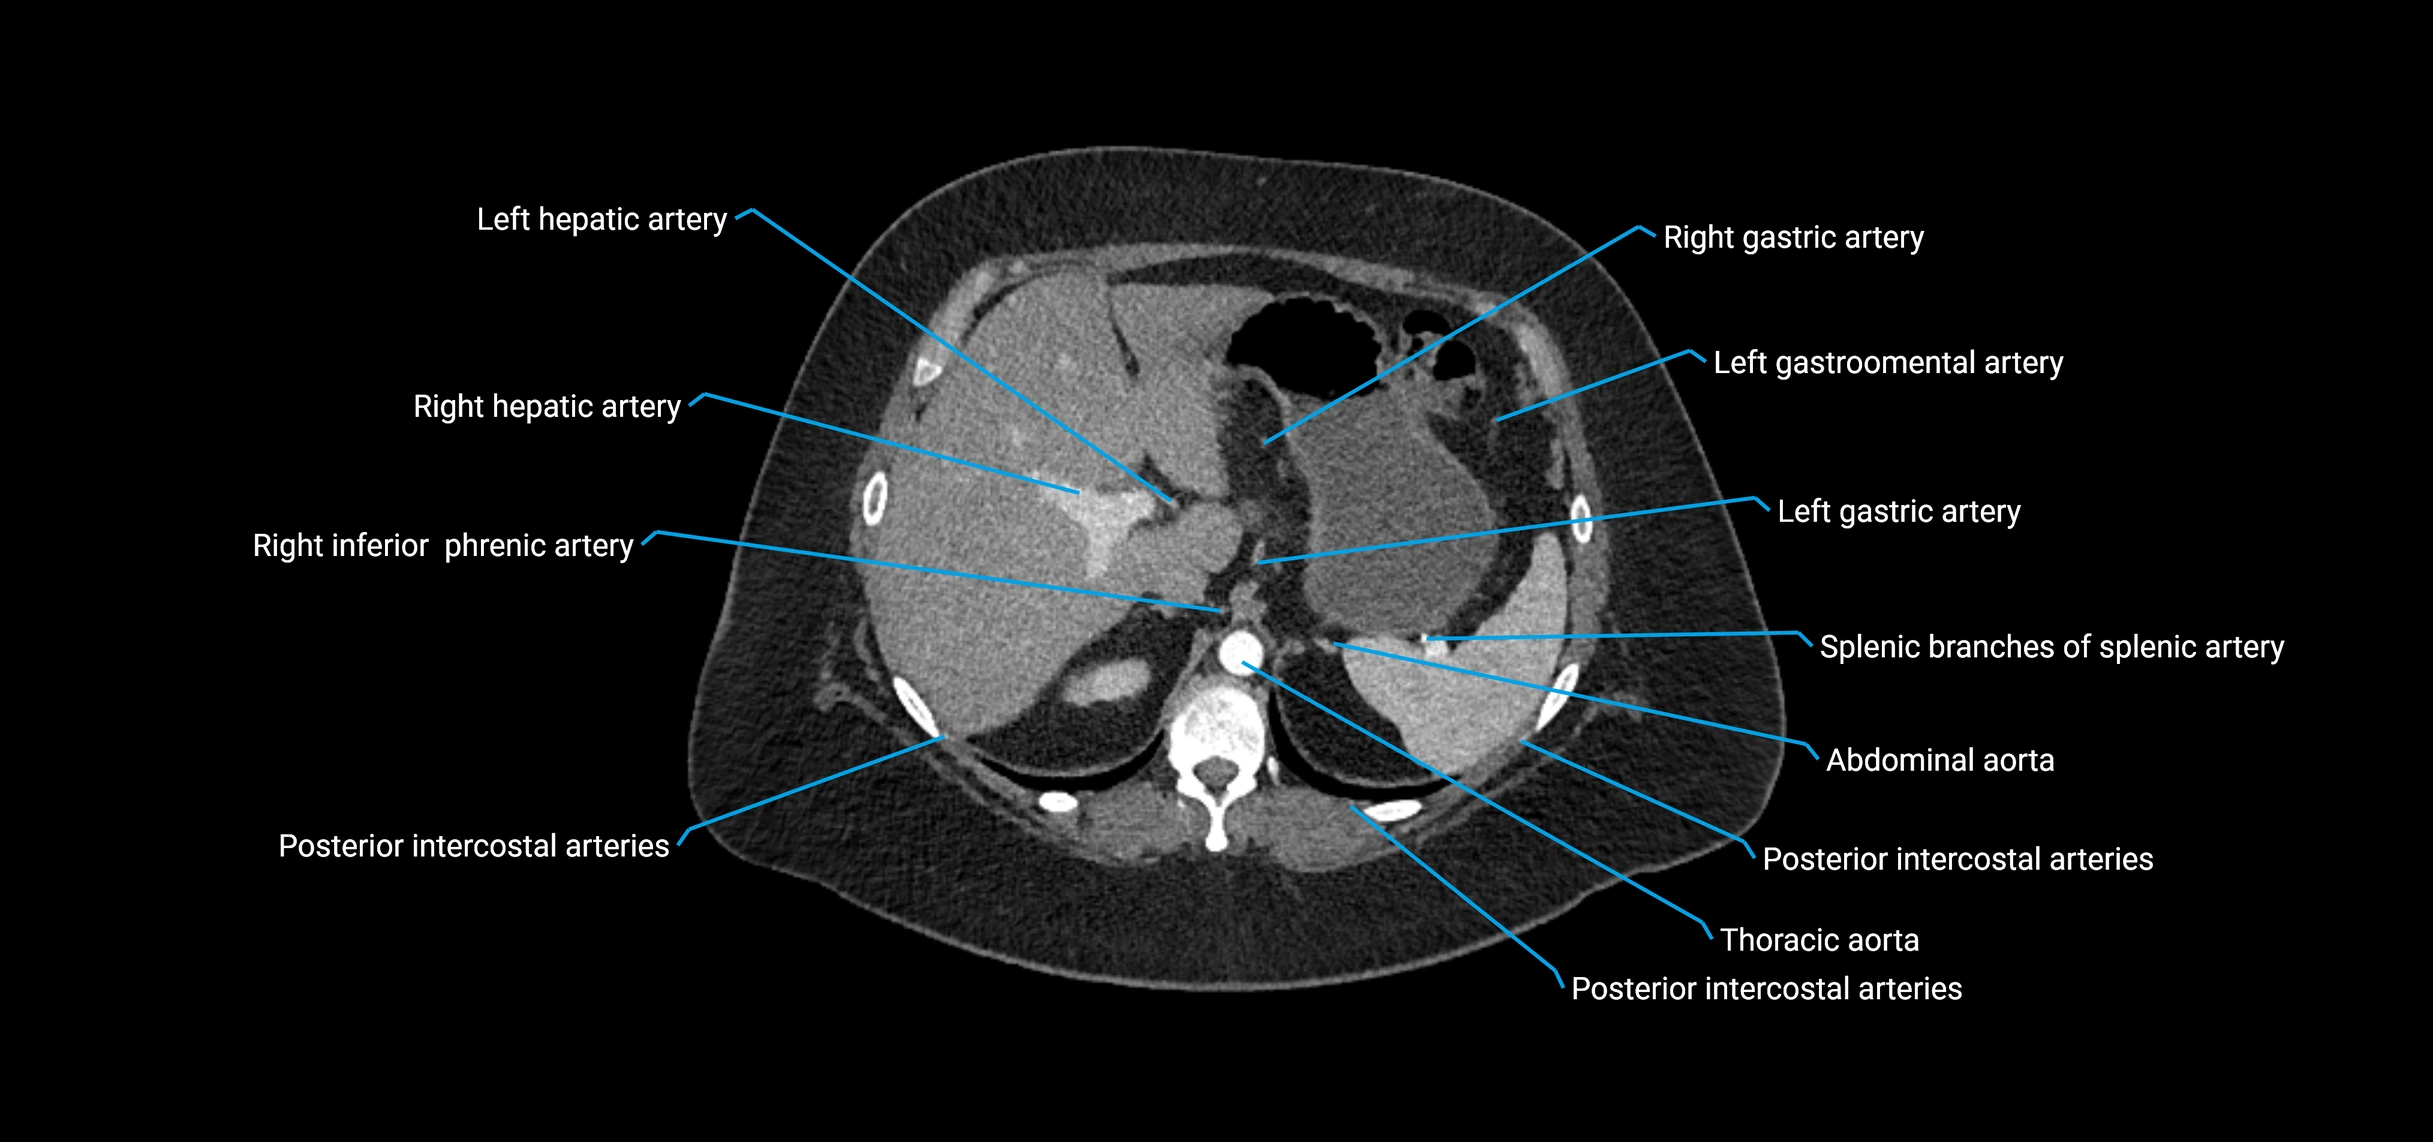

CT Appearance

Non-contrast CT:

• Appears as a tubular soft tissue structure anterior to vertebral bodies

• Calcified atherosclerotic plaques appear as hyperdense foci along the wall

• Useful for screening abdominal aortic aneurysm (AAA) size and mural calcification

Contrast-enhanced CT (CTA):

• Gold standard for abdominal aortic imaging

• Provides excellent detail of lumen, wall, aneurysm, thrombus, and branch vessels

• Multiplanar and 3D reconstructions help in aneurysm measurement, stent graft planning, and dissection evaluation